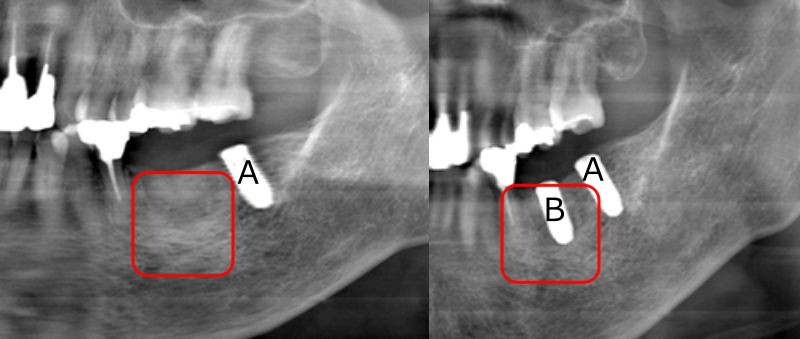

左がCGF併用によるGBRから3ヶ月後のX線写真。

赤で囲った部分がGBRを施した箇所で、少し白っぽく見えています。

右は更に3か月後のX線写真で、GBRから5か月でインプラントBを埋入しました。

右隣の、元々骨のあるところに埋入したインプラントAと比べても骨の状態に殆ど遜色は見られません。